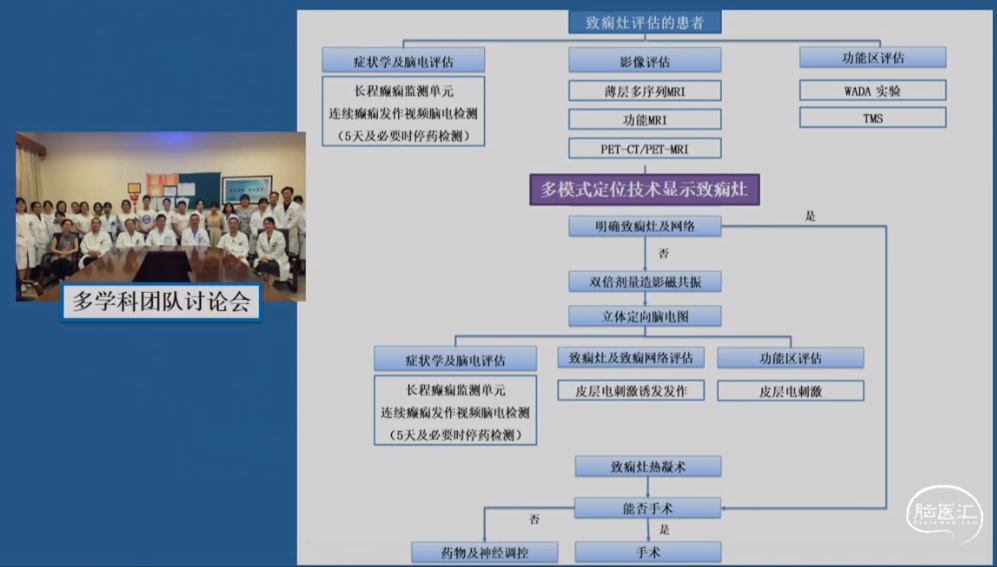

肿瘤手术? 癫痫手术?

•多团队合作进行诊断和治疗 -神经内科、神经外科(癫痫外科)、电生理、影像

•术前评估非常重要

-脑电(头皮EEG、侵袭性EEG)

-各种影像(MRI、PETCT...)

•确定手术切除范围

-单纯病灶切除?

-扩大切除?(双重病变:胶质增生、海马硬化、皮层发育不良...;累及颞叶的病变常需要做前颞叶切除+海马杏仁核切除)

难治性癫痫致痫灶评估的“中山模式”